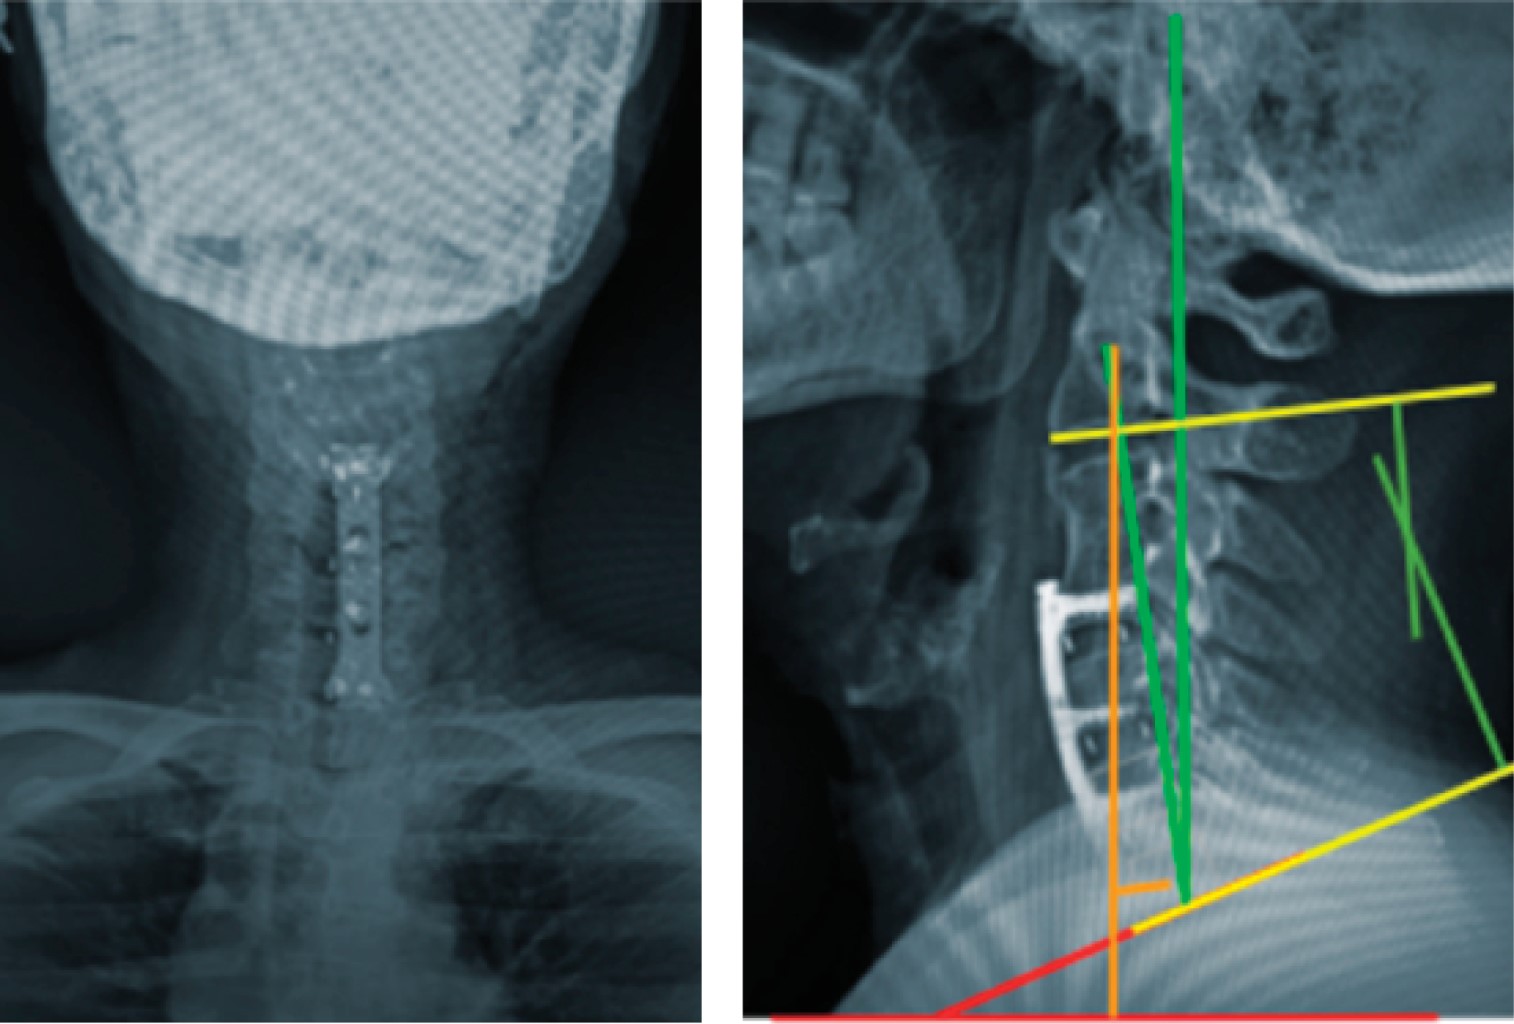

Figure 4